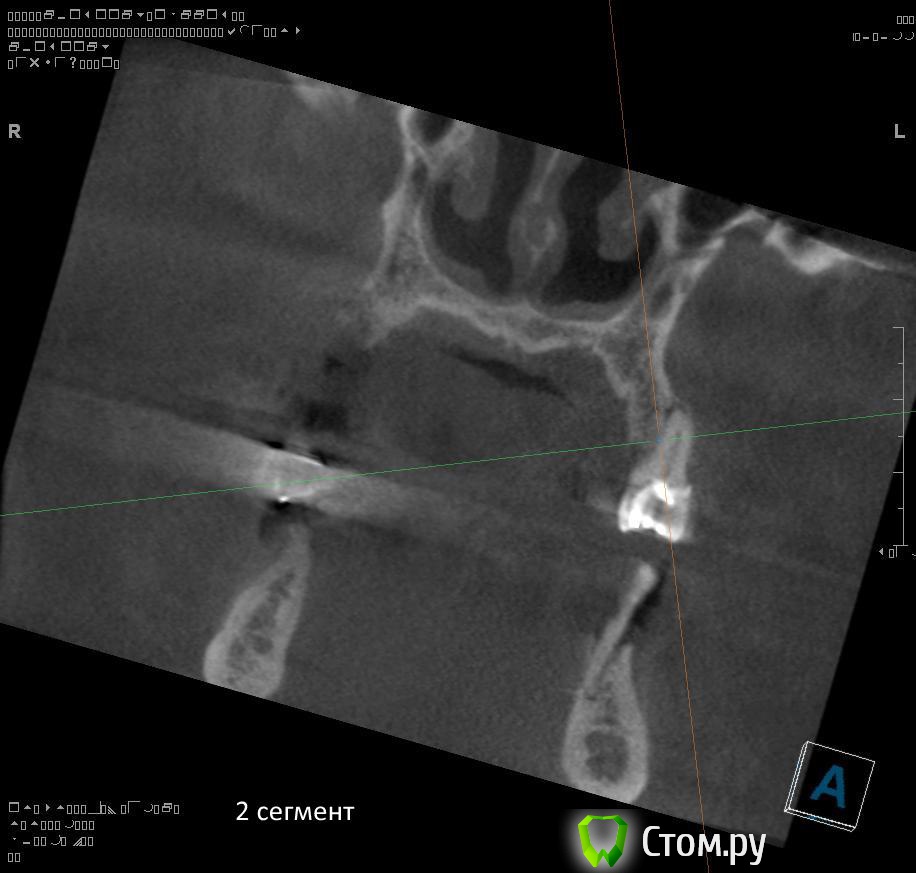

7. через 2-3 месяца после удаления 2.4, 2.5, 2.6 провести открытый синуслифтинг во втором сегменте возможно с одномоментной установкой имплантатов?

8. в какие позиции должны быть поставлены имплантаты во 2 сегменте (2.5, 2.6?)?

1. Не правильно понимаете. Покажите ЛОРу на предмет хронического гайморита и инородных тел в пазухе.